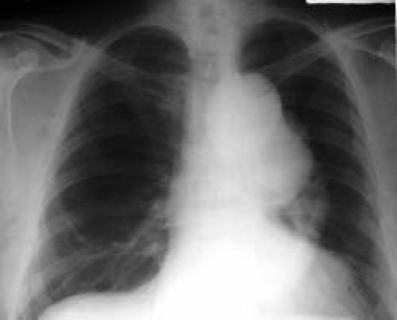

ДИАГНОСТИКА

При установлении диагноза необходимо проведение следующих исследований: рентгенконтрастная ангиография, спиральная комьютерная ангиография, рентгенография грудной клетки, эхокардиография (ультразвук сердца), магнитно-резонансная томография (МРТ).